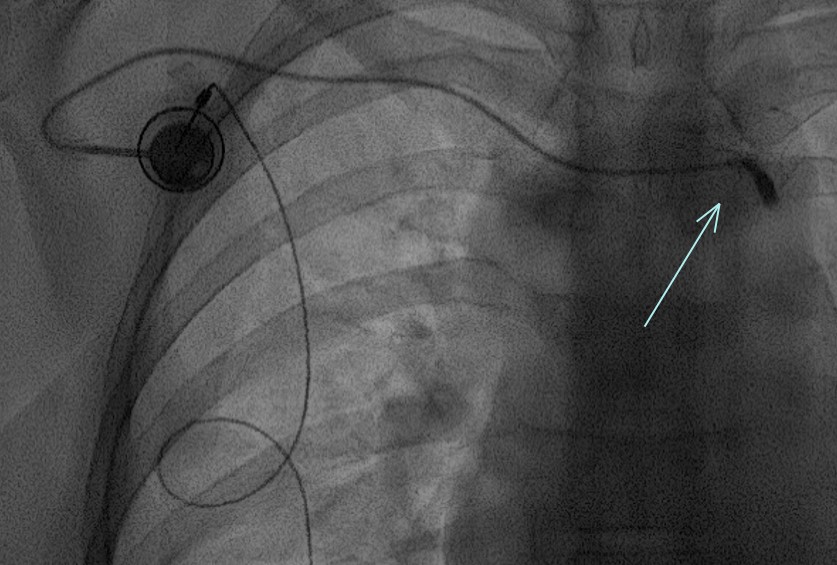

- “Twiddler Syndrome” = quand le patient joue avec les cables sous la peau et que ca les twist et les disloquent.

fracture du cable

Twiddler syndrome (avant / après)